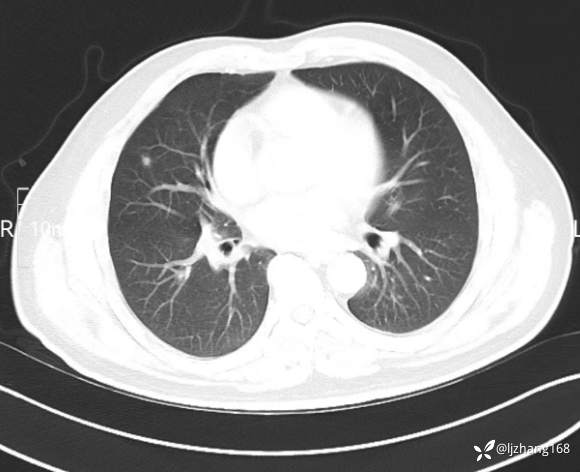

中年男患,右肺团片影,炎症0R肿瘤?

辅助检查:糖化血红蛋白12.3%。肺炎支原体IgG、IgM、呼吸道合胞病毒均未见明显异常。胸部CT:右肺上叶阻塞性肺炎。